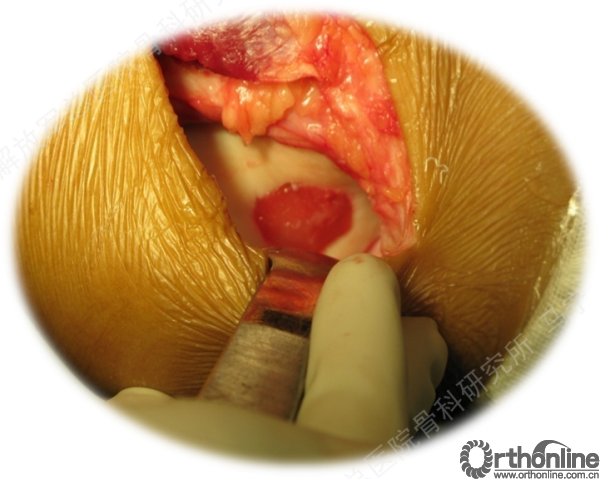

组织工程软骨植入:第二次手术-组织工程软骨回植。

软骨损伤区的清创。

软骨缺损范围的测量。

切开后可以看见很明显的软骨破坏。

对糜烂的软骨进行清创,按照损伤的面积裁剪软骨补片进行修补。

术中显示软骨损伤的面积比核磁上的范围要大很多。

上图是我们院自主研发的以软骨细胞外基质为原料的孔隙取向性支架。可以做成任意厚度任意大小,按照软骨缺损的形状裁剪好以后。这个损伤面积大概在4平方厘米左右。